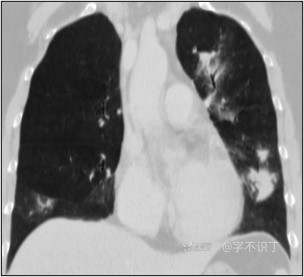

胸部病例讨论

患者性别:男

患者年龄:40岁

主诉:反复咳嗽2年,再发2月,咯血发热5天

简要病史:2年前无明显诱因出现阵发性干咳;2月前咳嗽症状较前加重,有少量白色粘液样痰,未经特殊处理,7天前咳嗽症状较前加重,伴咳黄脓样痰,痰中带血丝,予以哌拉西林舒巴坦+莫西沙星抗感染及祛痰等对症支持治疗,未觉好转,予以拉氧头孢、左氧氟沙星、布洛芬、氨溴索等对症处理,咳嗽、咳痰症状未缓解,仍有发热

体格检查:曾从事装修等工作,近半年从事煤矿管理工作。近期饮酒较频繁。既往有冶游史。

辅助检查:血液病原菌培养、分枝杆菌涂片检查、真菌涂片检查、一般细菌涂片检查、痰培养均阴性